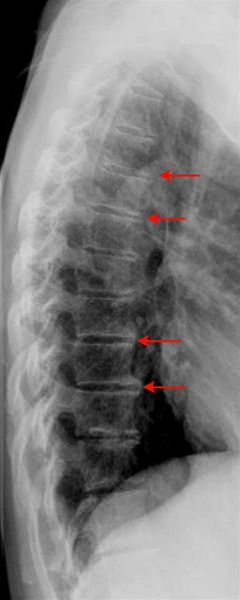

Sidebillede af thoracalcolumna med slitageforandringer i form af randudbygninger, det vil sige forkalkninger langs forkanten af ryghvirvlerne (pilene)